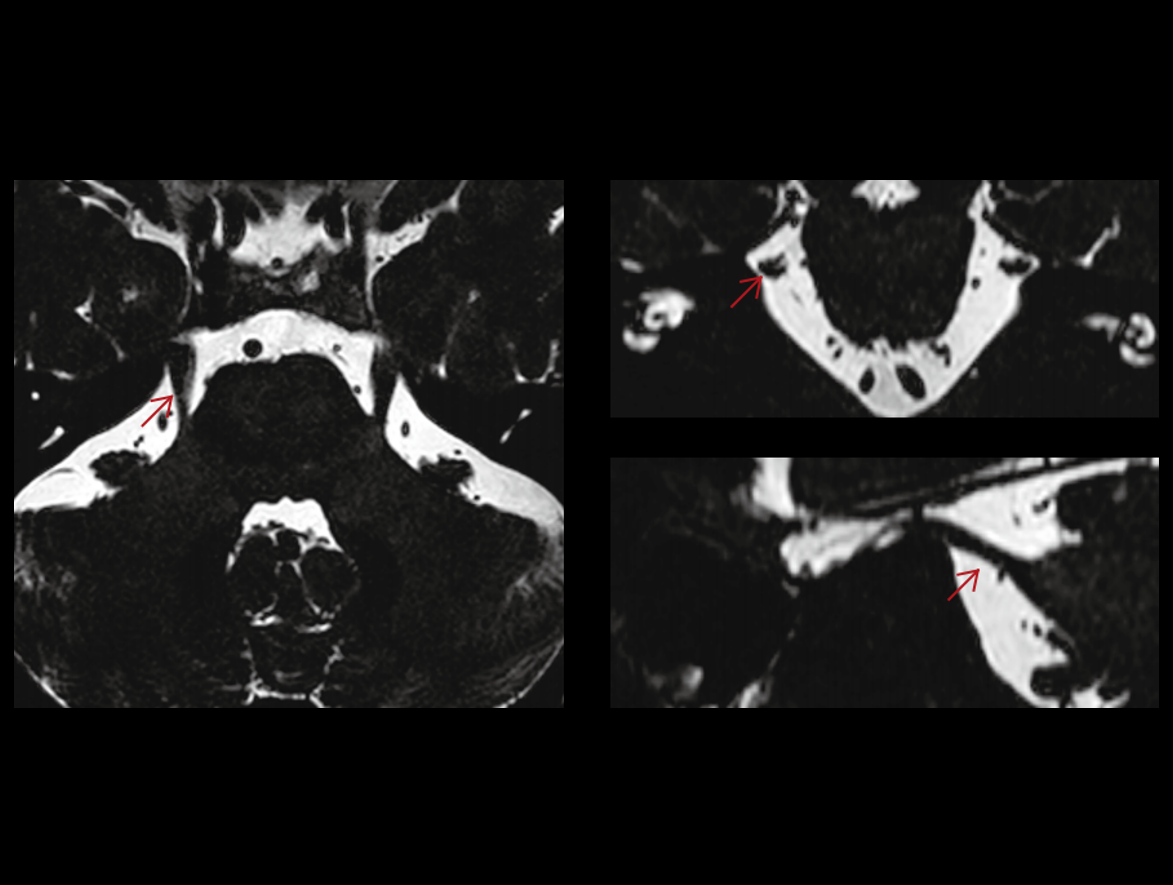

The high performance gradients improve data acquisition and scanning speed, which achieves higher work efficiency.

The 48 high-channel RF complements our integrated high-density coils, resulting insignificant image SNR increase.

The powerful 3.0T magnet uses a 170 cm short-magnet design to ensure high homogeneity of the magnetic field, which provides a solid foundation for fast imaging and excellent fat saturation over a large FOV, as well as outstanding off-center imaging.